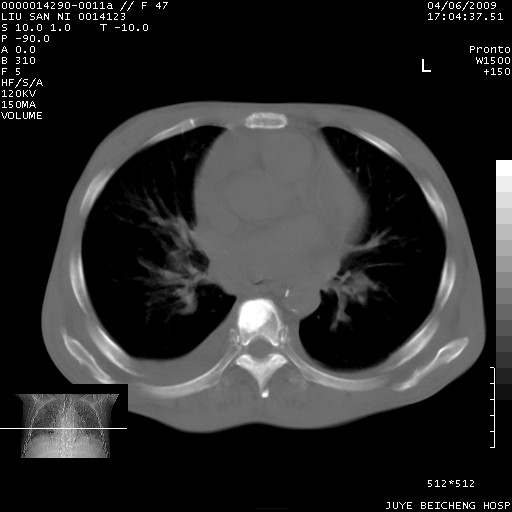

以下是引用前行在2009-4-7 10:31:00的发言:[br]肝脾肿大;双肾增大,双肾盂少量积水可能,肾膜膜增厚,肾周间隙增宽,并见桥间隔,提示结缔组系统疾病、系统性红瘢狼疮肾可能性大。继发右侧胸腔、心包、腹腔积液。